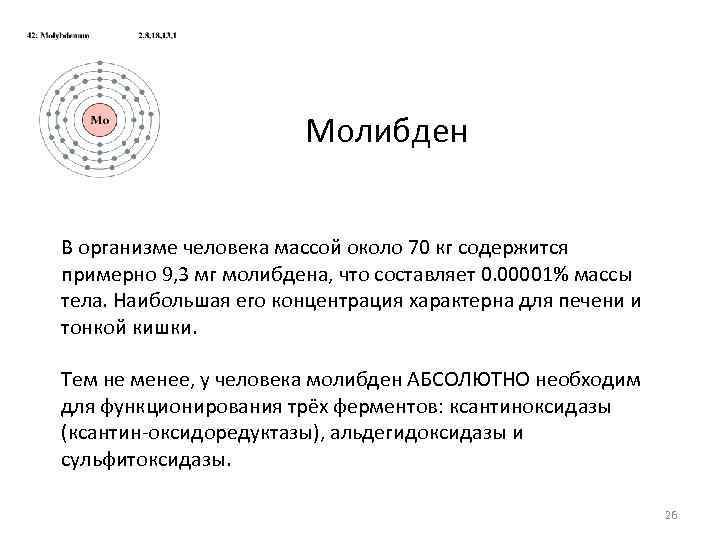

Молибден В организме человека массой около 70 кг содержится примерно 9, 3 мг молибдена, что составляет 0. 00001% массы тела. Наибольшая его концентрация характерна для печени и тонкой кишки. Тем не менее, у человека молибден АБСОЛЮТНО необходим для функционирования трёх ферментов: ксантиноксидазы (ксантин-оксидоредуктазы), альдегидоксидазы и сульфитоксидазы. 26